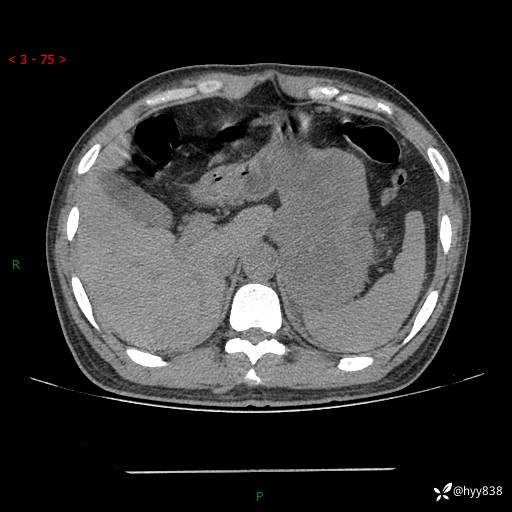

病例39岁/女,左侧腰痛入院。腹腔囊实性肿块,定位、定性---结果公布~

性别:男

年龄:39岁

简要病史:左侧腰痛待查,CT发现腹腔占位

腹部CT平扫+增强